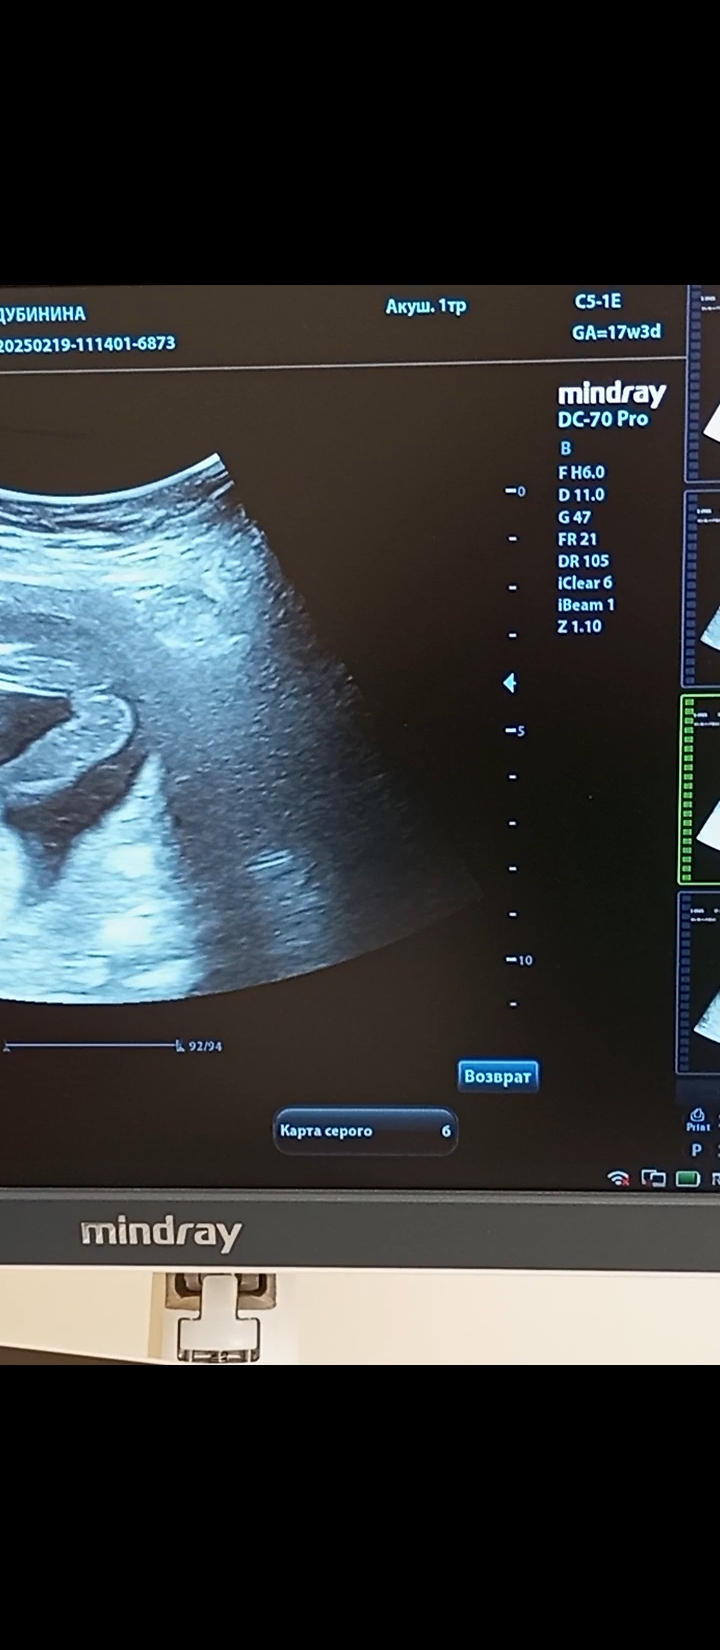

Валентина в Благополучная беременность 9 месяцев Кто тут? Мальчик или девочка? Пол малыша Кто тут? Посмотрите еще 20 записей на эту тему Лучший ответ Мама Лиля Вы уже раз 6 это фото выкладываете, вам пишут, что девочка, вы что хотите еще услышать? 28.02.2025 Ответить Мама Стифлера Мама Лиля, хочет услышать, что пиписька отросла судя по всему 28.02.2025 Ответить Ольга Галка, 😂😂😂 28.02.2025 Ответить Светлана Галка, может, к завтрашнему дню вырастет 28.02.2025 Ответить Отменить Ответить Анастасия Конечно, дочка ) 28.02.2025 Ответить Ornella Mutit Девочка💗 28.02.2025 Ответить Кошка В Сапожках Девочка 100% 28.02.2025 Ответить Виктория Девочка 28.02.2025 Ответить Дашик Девочка. Мне кажется мальчиков сразу видно. 28.02.2025 Ответить Eva Девочка тут явная) Ничего не торчит 01.03.2025 Ответить Ольга У вас мальчик 100%! Без сомнений! 😂 28.02.2025 Ответить Пол малыша Пол по узи Чаты Беременных Выберите чат: Январята-2026 Февралята-2026 Мартята-2026 Апрелята-2026 Майчата-2026 Июнята-2026 Июлята-2026 Августята-2026